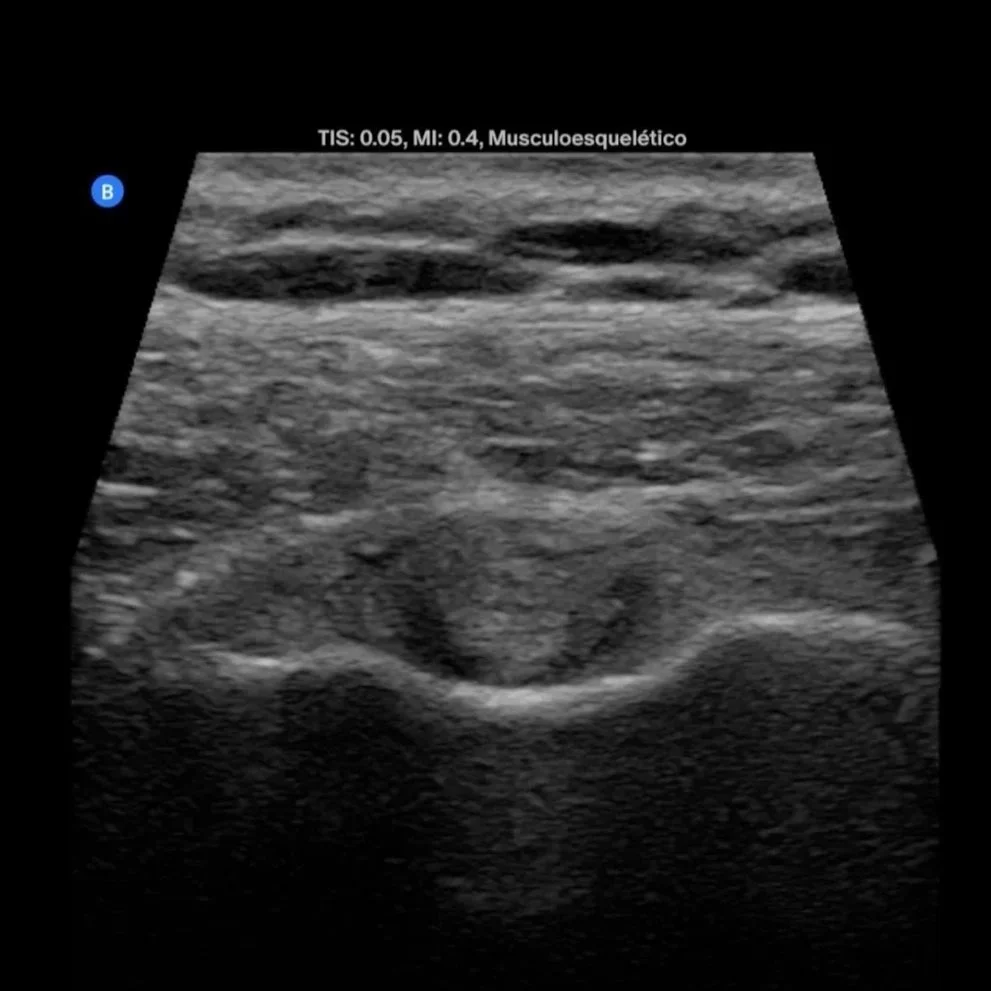

Una ecografía musculo esqueletica mostrando un tendón y un músculo.

Tendinitis de hombro